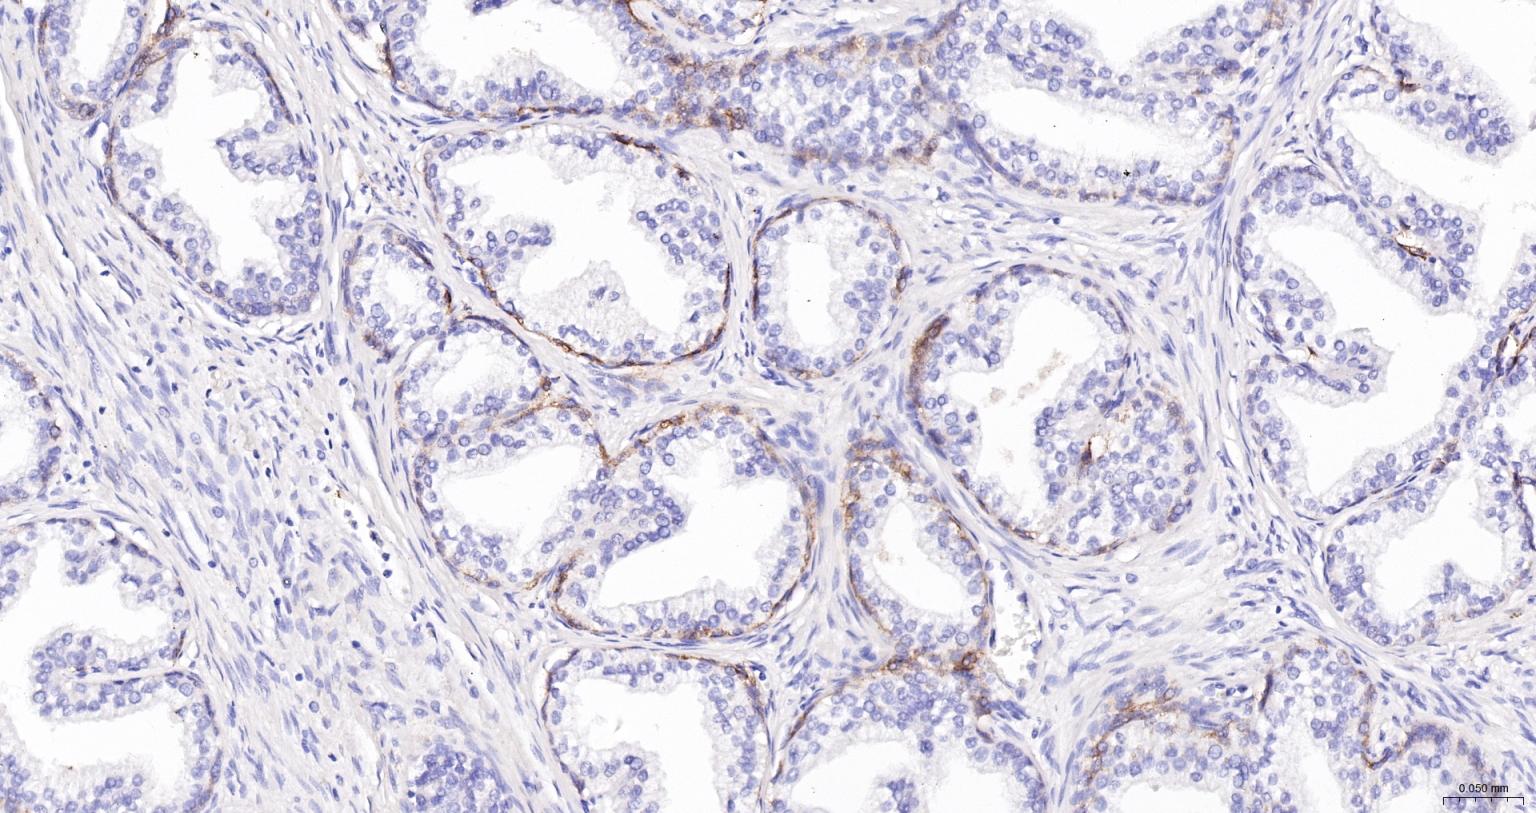

IHC-PHuman1:100-500

交叉反应: Human